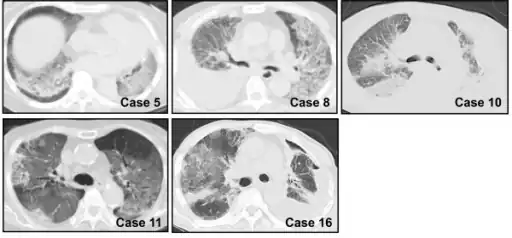

Rapid progression from initial symptoms to respiratory failure is a key feature. An X-ray that shows ARDS is necessary for diagnosis (fluid in the small air sacs (alveoli) in both lungs). In addition, a biopsy of the lung that shows organizing diffuse alveolar damage is required for diagnosis. This type of alveolar damage can be attributed to nonconcentrated and nonlocalized alveoli damage, marked alveolar septal edema with inflammatory cell infiltration, fibroblast proliferation, occasional hyaline membranes, and thickening of the alveolar walls. The septa are lined with atypical, hyperplastic type II pneumocytes, thus leading to the collapse of airspaces. Other diagnostic tests are useful in excluding other similar conditions, but history, X-ray, and biopsy are essential. These other tests may include basic blood work, blood cultures, and bronchoalveolar lavage. The clinical picture is similar to ARDS, but AIP differs from ARDS in that the cause for AIP is not known.